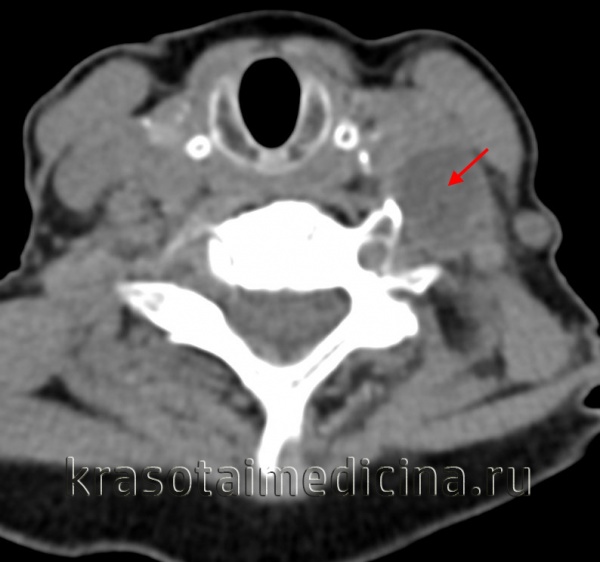

(Слева) КТ с контрастированием, аксиальный срез: определяется крупное поликистозное двустороннее образование шеи, почти полностью смещающее все нормальные ткани по окружности. У этого двухдневного новорожденного томограмма была получена для оценки распространения образования и планирования чрескожной склеротерапии.

3. КТ при лимфангиоме:

• Образование с четкими или нечеткими контурами

• Дольчатое с гиподенсными кистозными областями:

о Кистозные области не накапливают контраст

• Могут прорастать или смещать соседние органы

• Кальцификаты встречаются редко